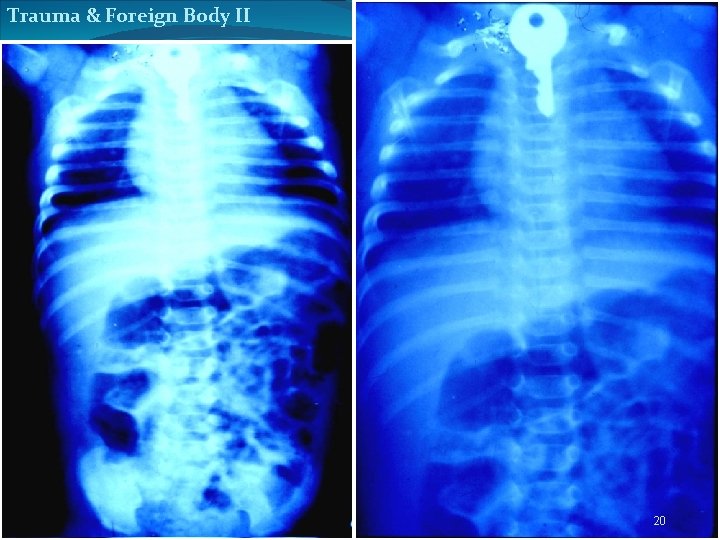

Trauma & Foreign Body II 20

Trauma & Foreign Body II hair pin flesh bolus 21

Trauma & Foreign Body II hair pin flesh bolus 23